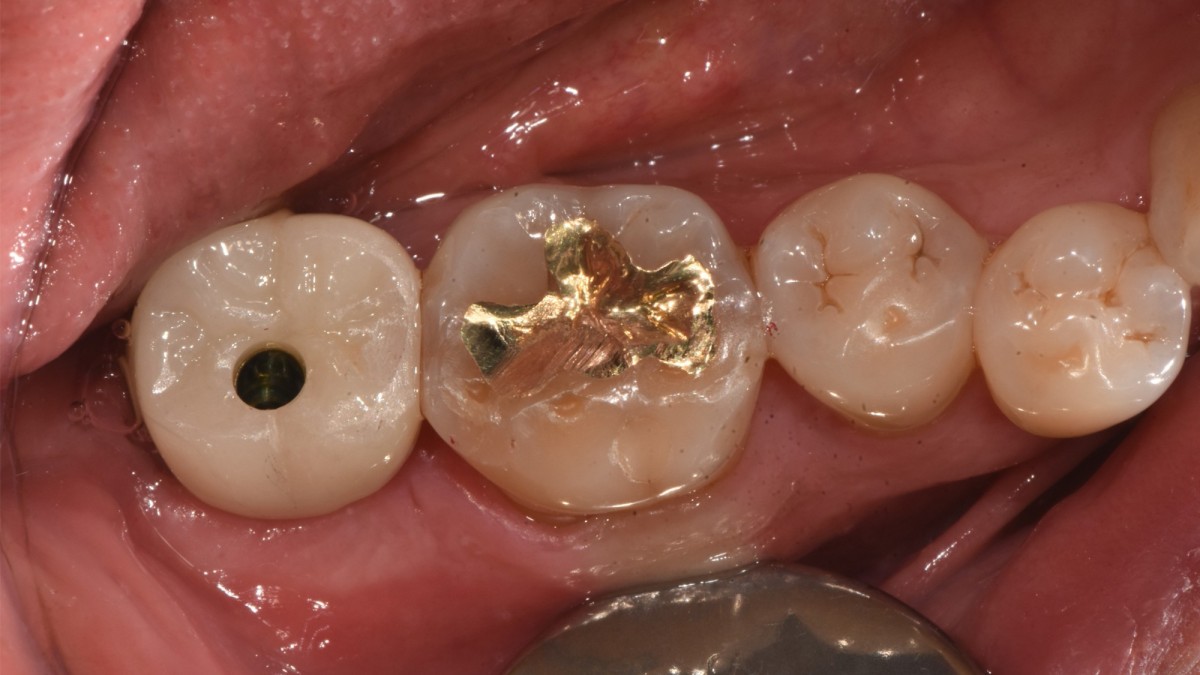

Single implant (staged) Arum NB1, f/u

▲Arum Dentistry NB1 5*10